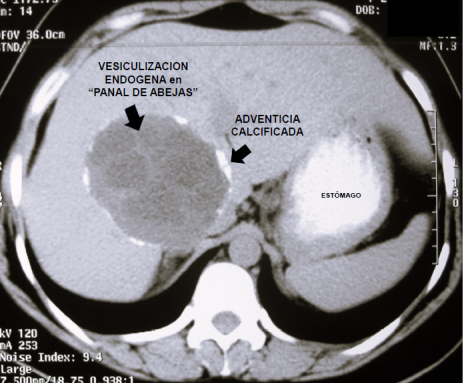

Esta comunicación muestra la correlación imagenológico-quirúrgica (Figura 1) de los estudios habituales para el diagnostico de quiste hidático en su forma crónica más frecuente: conteniendo "vesículas hijas" producto de la vesiculización endógena - responsable del signo patognomónico del “panal de abejas “ (Figura 2) - que es un indicador de vitalidad y complicación del quiste. La adventicia -muy gruesa y calcificada- se observa como una lámina blanca bien definida en la TC, (Figura 3) bajo forma de una lamina hipointensa en la RNM (Figura 4) e hiperecogénica en la ecografía (Figura 2) y corresponde a la reacción inflamatoria crónica del parénquima hepático por estimulo inmunológico de la lámina periquística hidática ,que en la evolución se infiltra de calcio .Las calcificaciones se visualizan mejor mediante TC. (Figura 3).La colangio-RNM es específica para establecer las relaciones quiste con el sistema biliar. (Figura 5)

Figura 3: Tomografia computarizada.(TC).. Muestra una visión más precisa de las áreas calcificadas periféricas y de la vesiculización endógena . Permite establecer las relaciones vasculo-biliares del quiste.